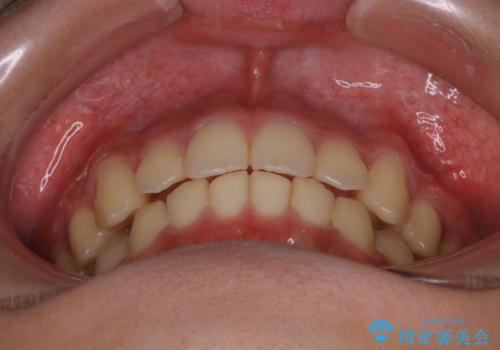

- 患者様、出っ歯のお悩みで来院されました。

骨格の分析を行ったところ上顎も出てはいるのですが、下顎が引っ込んでいる状態であるということがわかりました。

よって上顎の歯を抜いて治療をするのではなく、カリエールという器具を使用して下顎を前に引っ張り出しながら上顎を引っ込めるという治療を行うことにしました。